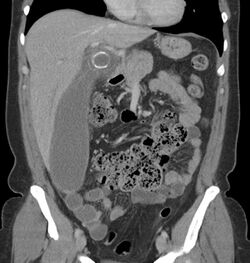

Where it is readily available, computed tomography (CT) has become frequently used, especially in people whose diagnosis is not obvious on history and physical examination. Although some concerns about interpretation are identified, a 2019 Cochrane review found that sensitivity and specificity of CT for the diagnosis of acute appendicitis in adults was high.[59] Concerns about radiation tend to limit use of CT in pregnant women and children, especially with the increasingly widespread usage of MRI.[60][61]

The accurate diagnosis of appendicitis is multi-tiered, with the size of the appendix having the strongest positive predictive value, while indirect features can either increase or decrease sensitivity and specificity. A size of over 6 mm is both 95% sensitive and specific for appendicitis.[62]

However, because the appendix can be filled with fecal material, causing intraluminal distention, this criterion has shown limited utility in more recent meta-analyses.[63] This is as opposed to ultrasound, in which the wall of the appendix can be more easily distinguished from intraluminal feces. In such scenarios, ancillary features such as increased wall enhancement as compared to adjacent bowel and inflammation of the surrounding fat, or fat stranding, can be supportive of the diagnosis. However, their absence does not preclude it. In severe cases with perforation, an adjacent phlegmon or abscess can be seen. Dense fluid layering in the pelvis can also result, related to either pus or enteric spillage. When patients are thin or younger, the relative absence of fat can make the appendix and surrounding fat stranding difficult to see.[63]